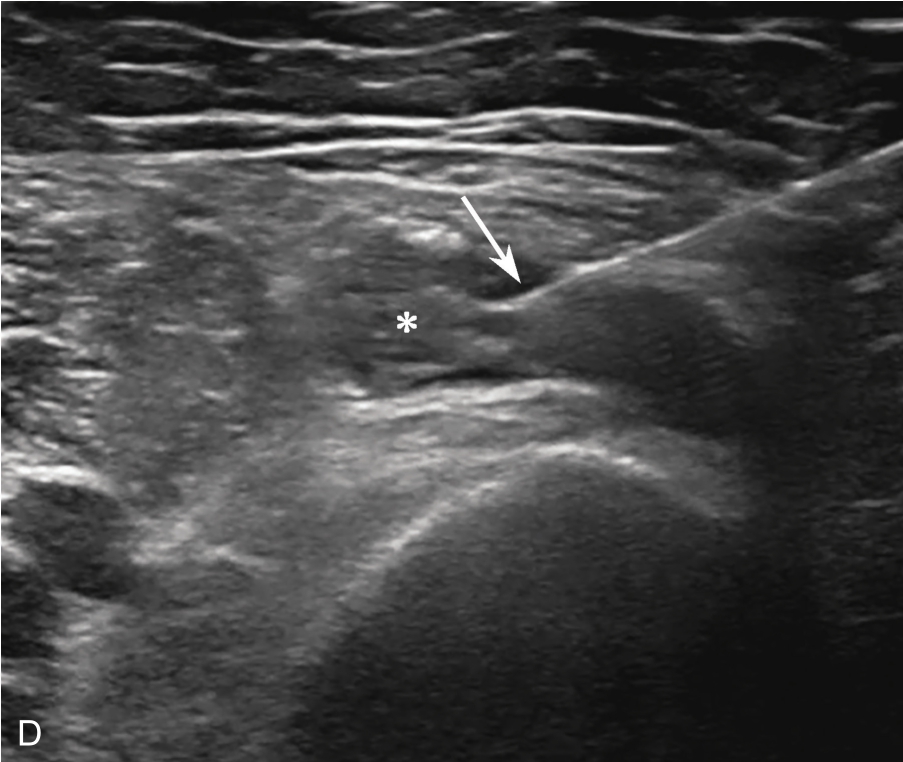

▲ 图2-1-11 超声引导下肩关节周围滑膜囊肿抽吸治疗超声图

A.超声引导下穿刺针进入滑囊前;B.穿刺针进入滑囊内;C.液体抽吸后,滑囊变小;D.超声引导下药物注射;星号:滑膜囊肿;箭头:穿刺针